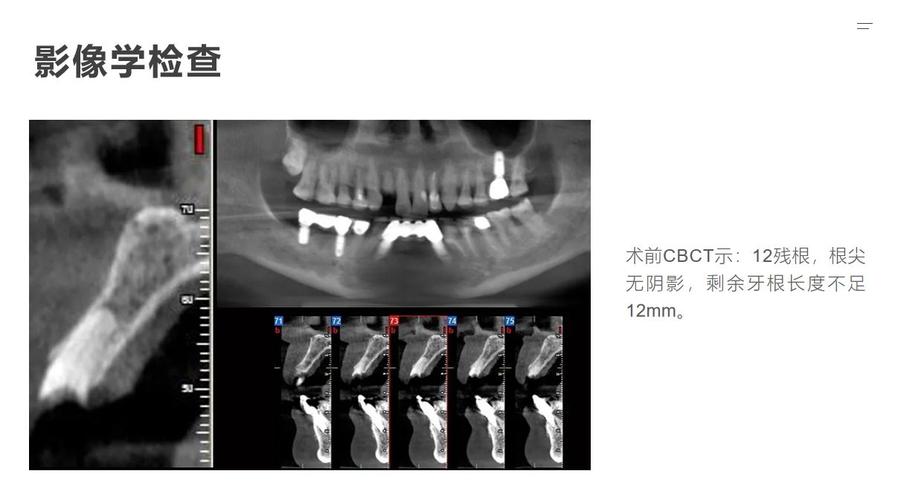

- 术前准备的不便: 可能需要拍CBCT等影像学检查,术前可能需要禁食禁水几小时,服用抗生素等药物。

- 骨愈合期: 骨粉(骨移植材料)需要时间与自身骨组织融合(骨结合),这个过程通常需要4-6个月,有时甚至更长,在此期间,绝对不能在手术区域进行任何操作,包括种植牙手术,医生会安排定期复查(拍CBCT或全景片)评估骨愈合情况。